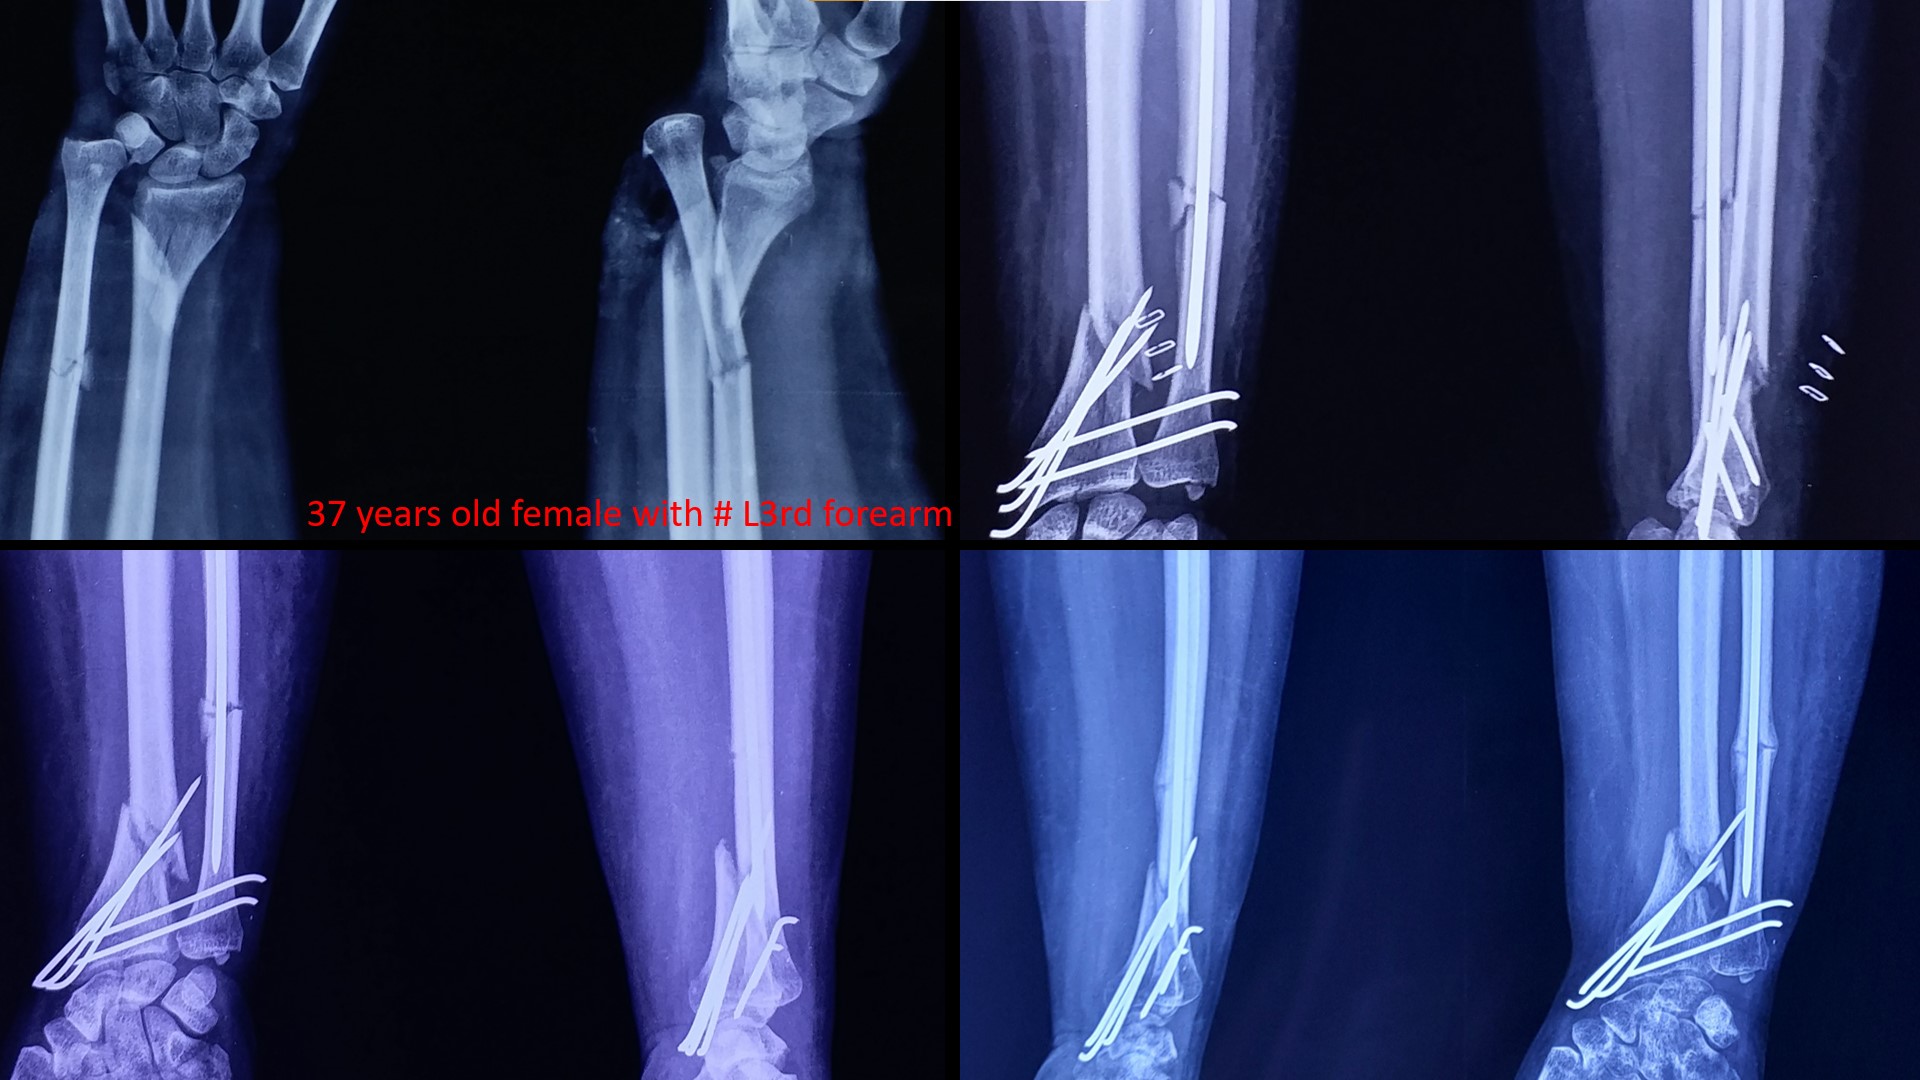

FRACTURE LOWER 3RD FOREARM